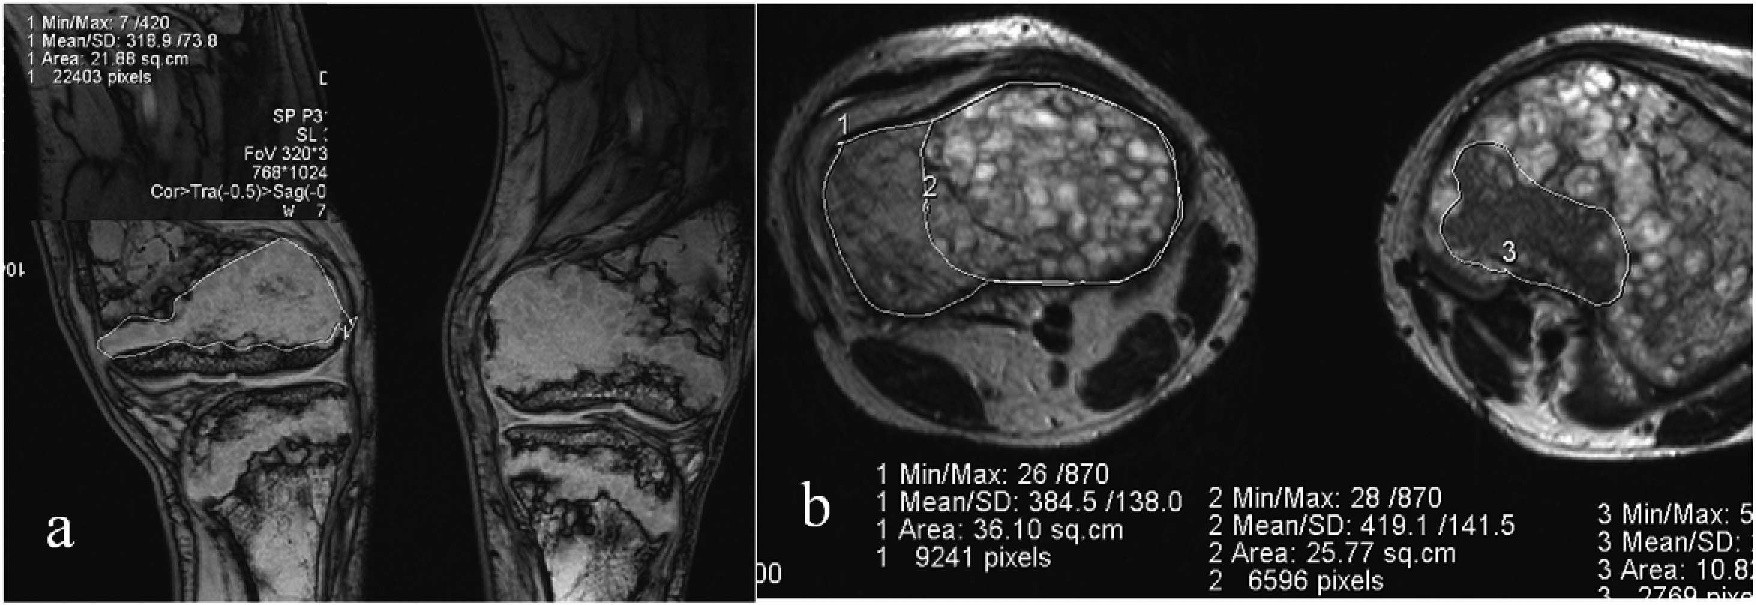

Fig. 1.Total and local bone density measured from cтscans of the knee joints. Topodramm (a), axial plane (b) of the proximal metaphysis of the right tibia in a 21- year-old patient.

- Preoperative CTfindings showed irregular trabecular patterns and greater distance between them in the femur and tibia metaepiphyses of 80% of the patients with VDR. Absence of typical cancellous bone pattern, thin cortex and lower density values in epiphyses and medial femur and tibia metadiaphyses were observed in patients aged 13–16 years. Bone density in the proximal tibial epiphysis showed greater values in all patients with D-resistant rickets aged 17 years–23 years as compared to the one in the distal femoral epi- physes.

Preoperative assessment of bone structure in patients with VDR aged 24 years–40 years showed areas of heterogeneous cancellous bone in both epiphyses and metaphyses. Bone structure of tibial and femoral metaepiphyses in patients with VDR aged 11 years–16 years appeared as scattered bone trabeculae medially and irregular sclerotic areas at one-to-two-year follow-ups. Patients aged 18 years–23 years showed greater sclerotic changes in the proximal tibial epiphyses and less changes in the distal femoral metaphyses at one-to-three year follow-up which is showed in Fig. 1.

Minimal bone density measurements were observed in the proximal tibial epiphysis of patients with VDR aged 24 years–30 years and deemed to be associated with extensive cysts at the level.